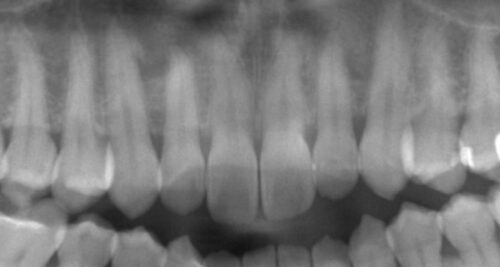

また、

レントゲンでも詰め物の奥で再びむし歯になっていないか等、

色以外にほかに問題点がないか検査が必要です。

今回はとくに問題ありませんでした。

ただ、古くなった詰め物は、

歯との接着面も劣化している可能性があるため、

一度除去して詰め直すことはむし歯対策として有効です。